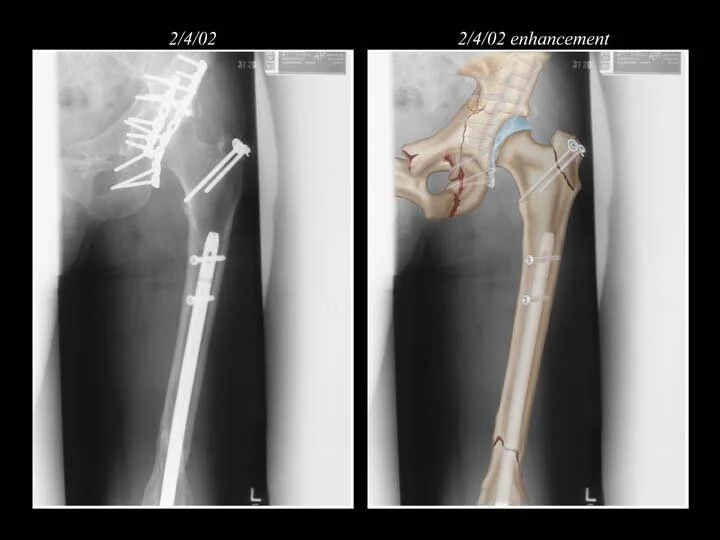

FILM ENHANCEMENT EXAMPLE 1

1. Film enhancement example